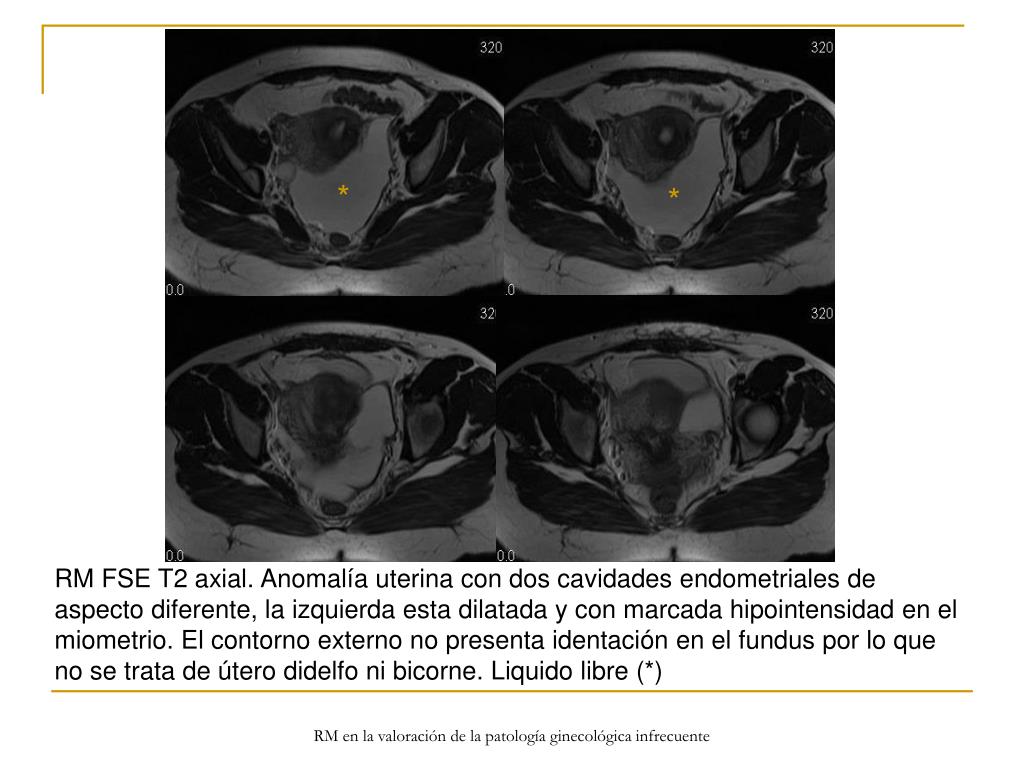

9. * * RM FSE T2 axial. Anomalía uterina con dos cavidades endometriales de aspecto diferente, la izquierda esta dilatada y con marcada hipointensidad en el miometrio. El contorno externo no presenta identación en el fundus por lo que no se trata de útero didelfo ni bicorne. Liquido libre (*) RM en la valoración de la patología ginecológica infrecuente